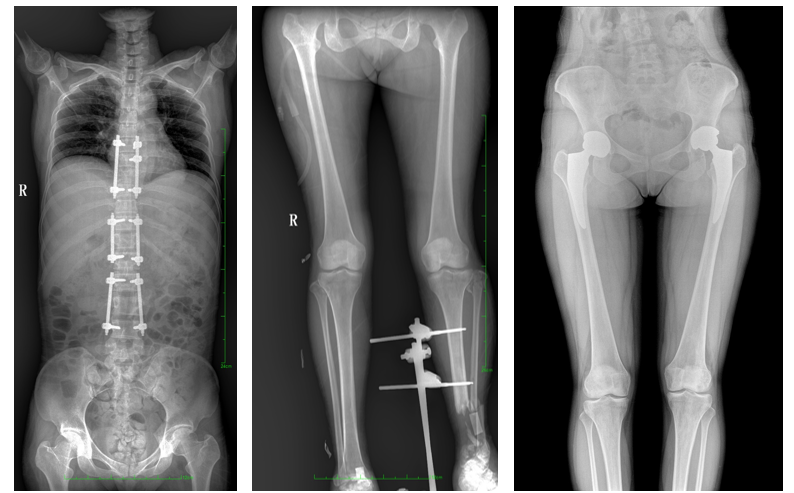

DR常用于人體胸部及骨骼攝片,也可拍攝其他部位,例如腹部、牙齒、頭顱等。使用人群較廣,可以進行全身各部位檢查,曝光后幾秒就可獲得數字影像,成像速度快,且價格便宜,極大提高了工作效率,方便臨床重癥、急癥患者的診治。

DR檢查

站立位X線影像是測定人體負重骨骼的生物學力線、對稱結構平滑線及脊柱側凸角等首選的檢查內容,這和CT、MRI臥位成像,在臨床意義上有著根本區別。在脊柱及下肢的臨床治療過程中,一般需要進行矯正和關節置換手術治療,在對其進行手術前后,均需要拍攝站立位負重X光片以便分析病情,明確診斷和觀察治療效果。

常規DR拍攝面積有限,最大規格僅有43cm,但成人男性全脊柱長度平均為70-75cm,女性為66-70cm,而雙下肢更長。普愛醫療PLX8600動態DR的43cm*86cm超大有效視野,可一次成像全脊柱及雙下肢。